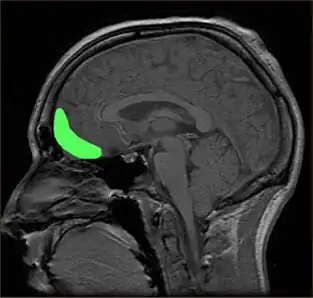

Prefrontal cortex

The prefrontal cortex is previously known for its roles in the perception of colored objects, decision making, and memory. Recent studies have also linked it to the conscious aesthetic experience because it is activated during aesthetic tasks such as determining the appeal of a visual stimuli. This may be because a judgment is needed, requiring visiospatial memory. In a study performed by Zeki and Kawabata, it was found that the medial orbito-frontal cortex (mOFC) is involved in the judgment of whether a painting is beautiful or not.[33] There is high activation in this region when a person views paintings which they consider beautiful. Other evidence shows that this same area is active during the experience of beauty derived from different sources,[43] including musical beauty[44] and moral beauty,[45] and even mathematical beauty.[46] Interestingly, experience of the sublime, as opposed to the beautiful, results in a different pattern of brain activity;[47] moreover, where it comes to judgment, although aesthetic and perceptual judgments leads t activity in the same brain areas, the pattern of activity is also different between the two, one of the most marked differences being the involvement of mOFC in aesthetic, but not in perceptual, judgments.[48] Surprisingly, when a person views a painting which they consider ugly, no separate structures are activated. Therefore, it is proposed that changes in the intensity of activation in the orbito-frontal cortex correlate with the determination of beauty (higher activation) or ugliness (lower activation). Additionally, the medial OFC has been found to respond aesthetics in terms of the context of which it is presented, such as text or other descriptions about the artwork. The current evidence linking the OFC to attributed hedonistic values across gustatory, olfactory, and visual modalities, suggests that the OFC is a common center for the assessment of a stimulus's value.[36] The perception of aesthetics for these areas must be due to the activation of the brain's reward system with a certain intensity.

Additionally, the prefrontal dorsalateral cortex (PDC) is selectively activated only by stimuli considered beautiful whereas prefrontal activity as a whole is activated during the judgment of both pleasing and unpleasing stimuli.[6] The prefrontal cortex may be generally activated for directing the attention of the cognitive and perceptual mechanisms towards aesthetic perception in viewers untrained in visual arts.[18] In other words, related directly to a person viewing art from an aesthetic perception due to the top-down control of their cognition. The lateral prefrontal cortex is shown to be linked to higher order self-referential procession and the evaluation of internally generated information. The left lateral PFC, Brodmann area 10, may be involved in maintaining attention on the execution of internally generated goals associated with approaching art from an aesthetic orientation.[18] As previously mentioned, directing of attention towards aesthetics may have evolutionary significance.